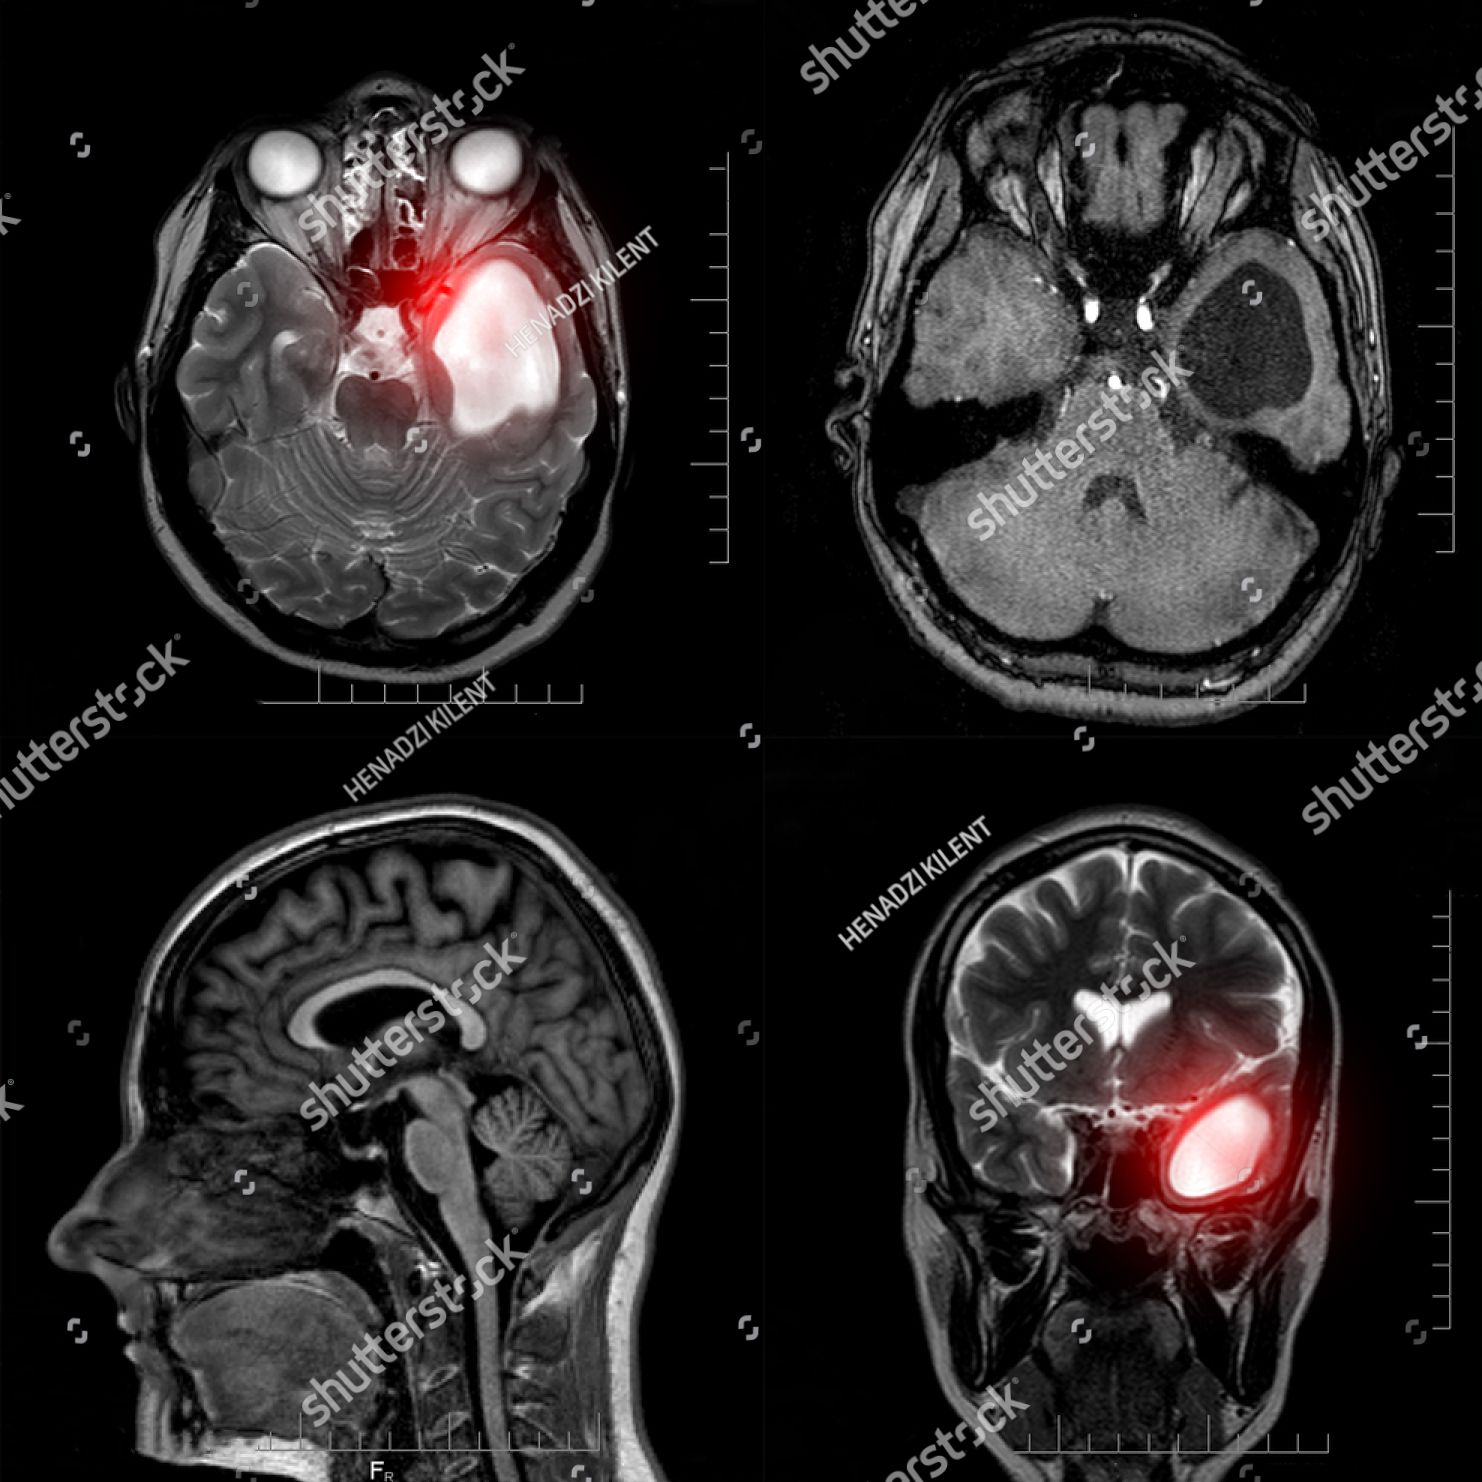

Die Tumore des zentralen Nervensystems werden entsprechend der weltweit gebräuchlichen und allgemein anerkannten WHO-Klassifikation der Hirntumore nach verschiedenen Kriterien eingeteilt und zugeordnet. Die Einteilung erfolgt erstens nach der mutmaßlichen Tumorzellenherkunft (benignes Muttergewebe), zweitens nach dem Grad der Bösartigkeit und letztens auch nach molekularen Eigenschaften (Gene, Gen-Amplifikation, -Deletion, -Translokation etc.).

Zur Abklärung von Raumforderungen im Schädelinnenraum eignen sich die Computertomographie (CT) und in erster Linie die Magnetresonanztomographie (MRT).